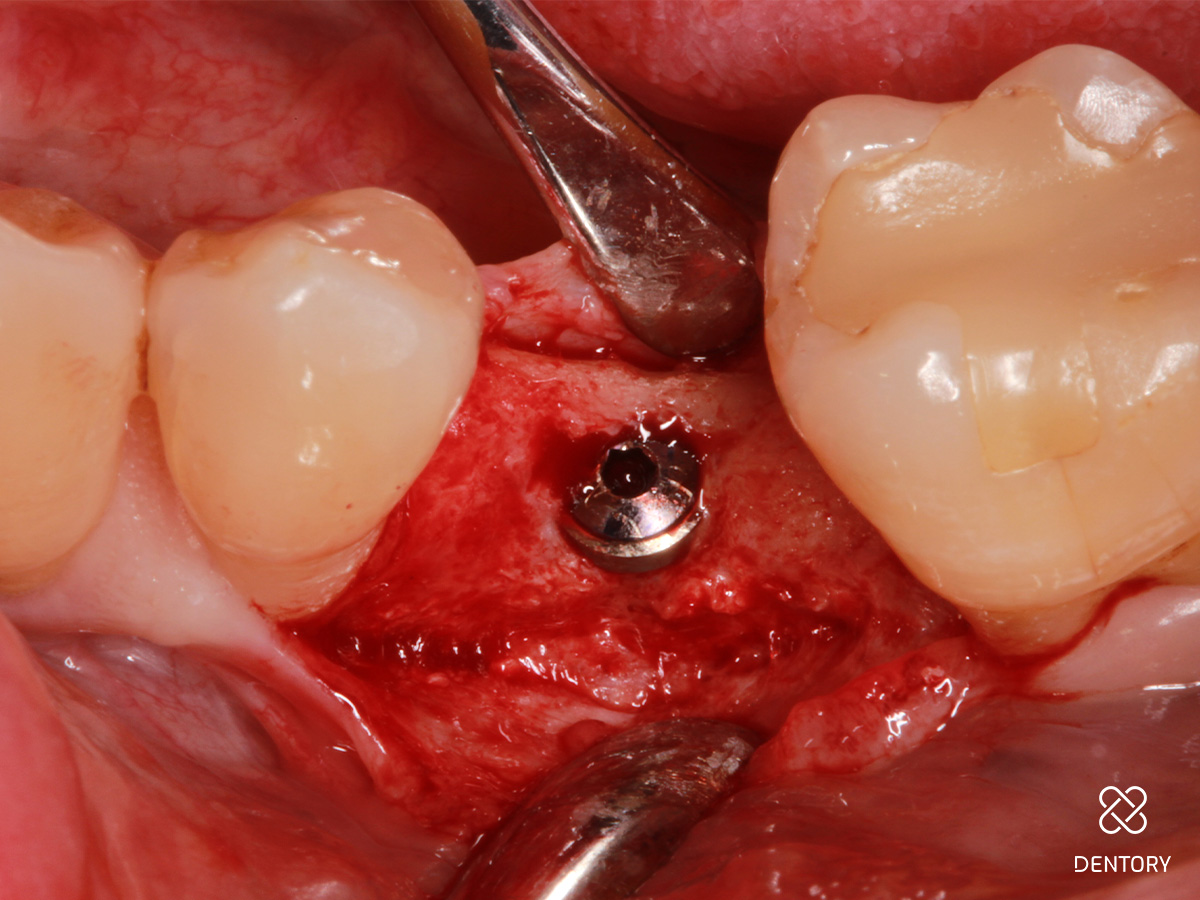

Abbildung 2

Simultane Implantation und GBR: Darstellung des späteren Implantatlagers nach Elevation eines Mukoperiostlappens; es zeigt sich ein horizontal ungenügendes Knochenangebot.